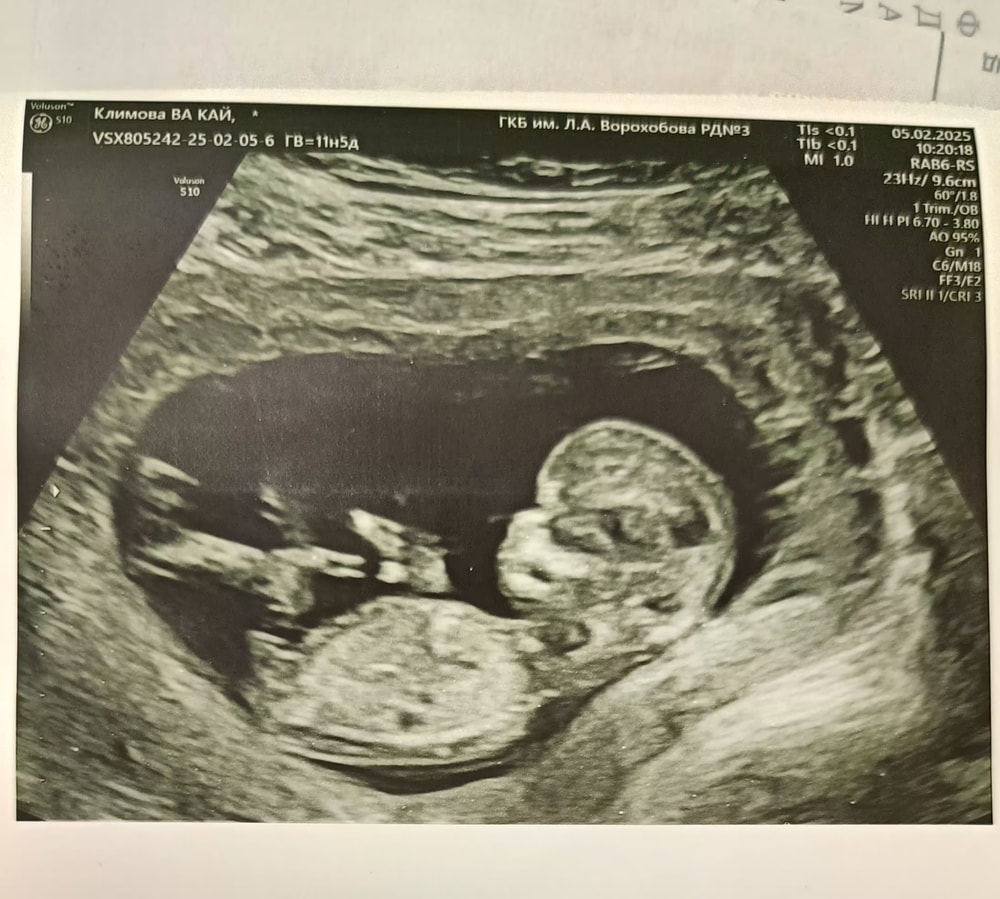

Виктория , а я наоборот пересмотрела узи всех тут на 9 неделе и вижу ноги :( а у меня их не вижу Изображение

Катя, на самом деле не всегда и в 12 н на снимке ноги и руки будут, каа выяснилось.У вашего разве не нога вверх торчит?

Одуванчик, слишком длинная для ноги мне кажется

Катя, думаю, вам кажется)в любом случае, у узитов глаз наметан, если б она не увидела рук или ног, она бы точно об этом сообщила.

Катя, на фото в посте ре уперся и там вообще непонятно как он ноги задрал, а они у него есть. И фото ниже этого коммента там у малыша тоже длинная нога

Одуванчик, удивительно, длинные ноги у родителей 160 и 170 ростом 😅😅😅Это я про нас

Катя, это снимок узи, наверняка, он может и пропорции искажать, на обычных то фото с разных ракурсов ноги то длинные, то короткие,а это узи

Вера, да, подобные я видела, когда "в воздухе" кружочки ступней и ладошек. Видимо, аппарат при таком ракурсе не отображает ног и рук. У вас и ножку видно, это же ножка, не пуповина?

Яна, по идее, раз ребенок в профиль, значит руки и ноги должны быть в кадре, но получается, ткани такие,что волны сквозь них проходят, раз их не видно?

Яна, получается, тоже часть ручки между кулачком и телом не видно. Значит, да, ткани пропускают волны сквозь себя. Скорей всего на фото в посте тоже и руки и ноги вверх задраны, просто их волны не отразили, потому что ребенок не мог их задрать так, чтоб они вдоль тела легли

Марина, я когда беременная была, ходили с мужем на УЗИ, он сразу всё быстро понимал что где и на снимках тоже, а мне нужно было фантазию включать). И вот на таких снимках вижу голову и тело, а рук и ног- не вижу и мне непонятно как малыш лежит, раз тело упирается, значит, ноги задраны вверх и по идее нижнюю часть тело не долдно быть видно , но ее видно, значит, ноги "прозрачные"🤔